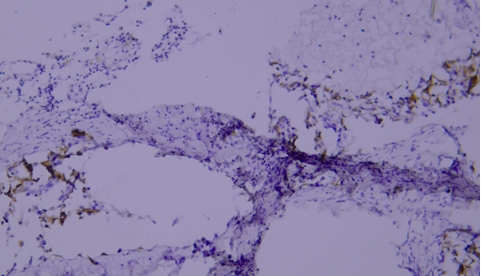

(V) Tissue Drying IssueTypical example:

TIMP-1 staining of paraffin-embedded human prostate tissue sections showed false negatives due to tissue drying (indicated by black arrows).

Recommendation for Resolution: Using a buffer supplemented with Tween-20 can effectively prevent section drying.